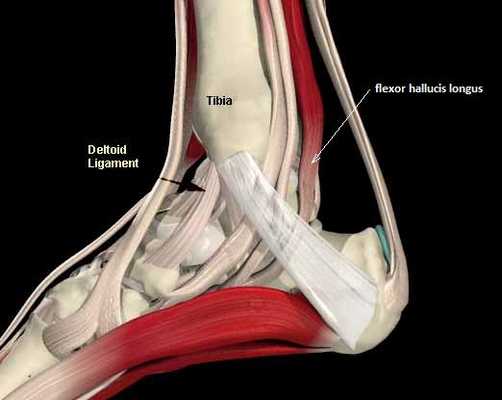

Вдоль передней, медиальной (внутренней) и латеральной (наружной) поверхности голеностопного сустава располагаются очень важные в функциональном отношении сухожилия. Это сухожилие передней большеберцовой мышцы, сухожилие задней большеберцовой мышцы, два сухожилия малоберцовых мышц (длинной и короткой). Мощное ахиллово сухожилие располагается позади голеностопного сустава и прикрепляется к пяточной кости. Оно также может поражаться при различных состояниях, о которых мы поговорим в отдельном разделе.

2. Брюшко задней большеберцовой мышцы начинается на задней поверхности большеберцовой и малоберцовой костей, а ее сухожилие идет вдоль задней поверхности внутренней лодыжки и на стопе прикрепляется к ладьевидной кости. Эта мышца осуществляет инверсию (внутреннюю ротацию) стопы и ее подошвенное сгибание в голеностопном суставе, однако основной ее функцией является поддержание продольного свода стопы. Сокращаясь, задняя большеберцовая мышца блокирует суставы среднего отдела стопы при ходьбе, и стопа тогда работает как жесткий рычаг. Разрыв сухожилия этой мышцы или даже его перерастяжение приводит к развитию плоскостопия.

Задняя большеберцовая мышца активна в течение фазы опоры, включается сразу после контакта пятки с опорой и быстро прекращает сокращаться после поднятия пятки. Ее брюшко начинается глубоко внутри задней части нижней конечности, сухожилие следует вниз до задней части медиальной лодыжки, где находится кпереди от сухожилия длинного сгибателя пальцев, заднего большеберцового нейрососудистого пучка (задняя б/б артерия, вена и нерв) и сухожилия сгибателя большого пальца. Все эти структуры ограничиваются удерживателем сгибателей возле медиальной лодыжки. Сухожилие задней б/б мышцы проходит в борозде позади и ниже медиальной лодыжки, разделяясь на 3 части у медиальной стороны тарана. Передняя часть прикрепляется к бугристости ладьевидной кости, средняя часть продолжается в плантарную тарзальную область и прикрепляется к плантарной части клиновидных костей, кубовидной и в основании 2, 3 и 4 метатарзальных костей. Задняя часть внедряется как пучок в переднюю часть нижней пяточно-ладьевидной связки. Медиальная лодыжка работает как многороликовый блок, позволяя сухожилию задней б/б мышцы изменять направление тяги, и эти точки прикрепления обеспечивают супинацию заднего и среднего отделов стопы во время переноса веса, в то время как происходит стабилизация арочной конструкции среднего отдела.